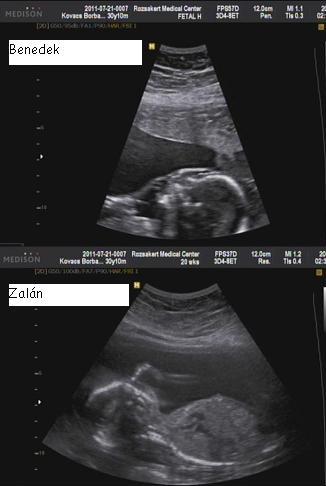

most lehet, hogy butaságot kérdezek, de hogy fogjátok eldönteni, hogy melyik baba melyik nevet kapja? :D Ránézésre, vagy amelyik először megszületik, az lesz Benedek? Vagy fordítva?

Leeda, ami nevek ott vannak azok már a babákhoz tartoznak. A baba van közelebb a "kijárathoz" B van feljebb. Így lesznek A és B baba. Igazából helyet már nem cserélnek mert a lepénynek fix helye van na és még a méret is ott van. Tudjuk,h A baba kisebb mint B. Én mindenképpen a kisebbnek szerettem volna a Benedek nevet :) más kérdés ami a hétvégén felmerült,h mi van,ha pont fordítva illenének rájuk a nevek, de próbálok hinni a megérzésben :)